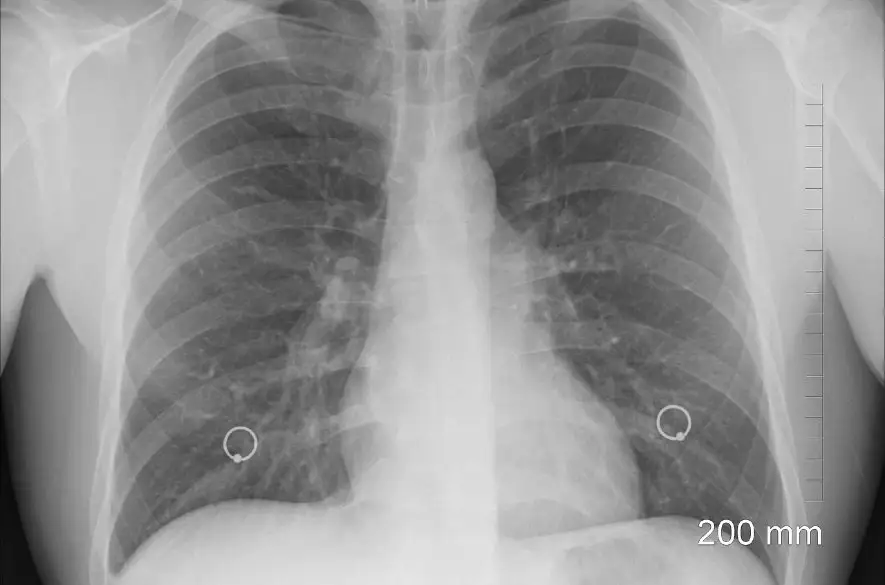

Ochorenia dýchacej sústavy sú treťou najčastejšou príčinou úmrtí, hneď po kardiovaskulárnych ochoreniach a rakovine. V rebríčku najčastejších príčin hospitalizácie sa nielen na Slovensku dlhodobo umiestňuje zápal pľúc - pneumónia.

Zápal pľúc je často spôsobený baktériou Streptococcus pneumoniae. Je to vážne ochorenie, ktoré môže byť život ohrozujúce. Najviac prípadov ochorenia sa vyskytuje v zime,

čo je spôsobené zníženou obranyschopnosťou organizmu, zvýšeným výskytom chorôb dýchacieho ústrojenstva a rýchlym a ľahkým prenosom baktérií kvapôčkami. Inkubačná

doba, tzn. čas od nákazy po vypuknutie prvých príznakov, sa odhaduje na 1 až 3 dni. Ide o infekčné ochorenie, tzn. že nie je možné zápal pľúc dostať len z prechladnutia.

Zápal pľúc postihuje 35 000 Slovákov ročne 3 , je jednou z najčastejších príčin hospitalizácie u nás a zároveň patrí medzi ochorenia s najdlhšou ošetrovacou dobou v nemocnici.